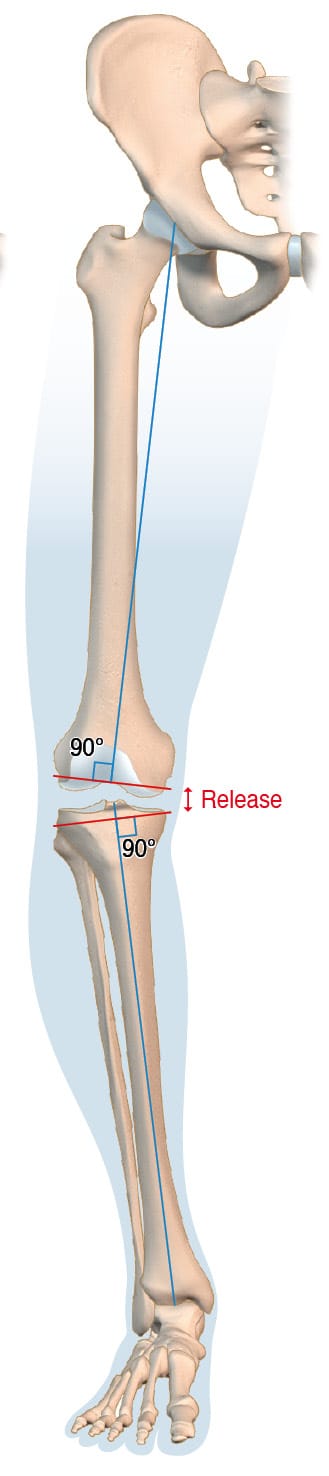

Mechanical alignment (MA) in TKA aims for a straight alignment of 180° ± 2° along the mechanical axis of the lower limb. This axis extends from the center of the femoral head, through the knee, and to the center of the ankle—forming the Hip-Knee-Ankle angle. Precise cuts are made at 90° to both the femur’s and the tibia’s mechanical axes. (Figure 3) This surgical technique, outlined by Insall et al. in 1982, is widely regarded as the gold standard for TKA [4] Insall JN, Binazzi R, Soudry M, Mestriner LA. Total knee arthroplasty. Clin Orthop 1985:13–22.. The rationale for these perpendicular cuts is to ensure even load distribution across the prosthesis, thus reducing wear and risk of aseptic loosening. Nonetheless, this technique has been critiqued for its necessitation of ligament release, which can result in suboptimal gap balancing—potentially contributing to the dissatisfaction experienced by 10-20% of TKA patients. These challenges with gap balancing have led surgeons to explore new alignment strategies that better balance the gap while more closely approximating the patient’s native knee anatomy.